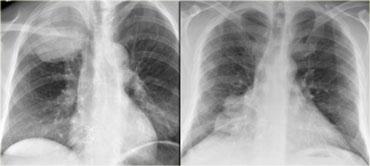

Bên trái là hình ảnh của hai bệnh nhân khác nhau.

Hãy mô tả các dấu hiệu và tiếp tục.

Trên phim X-quang bên trái, có một tổn thương tạo góc nhọn với trung thất.

Đây phải là một khối u phổi.

Phim X-quang ngực bên phải cho thấy một tổn thương tạo góc tù với trung thất.

Đây phải là một khối u trung thất.

Do có dấu hiệu bóng mờ xóa bờ tim phải – vốn nằm ở phía trước – chúng ta có thể suy luận rằng khối u phải nằm trong trung thất trước.

Tổn thương bên trái là u Pancoast.

Tổn thương bên phải là u tuyến ức (thymoma), nằm trong trung thất trước.